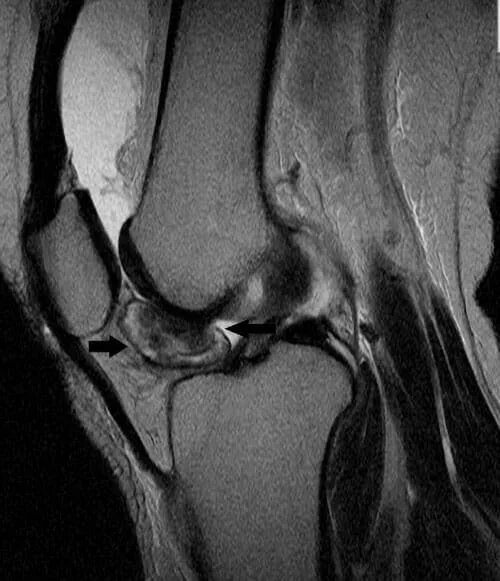

Пигментный виллонодулярный синовит